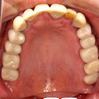

- プラタナス会独自のノウハウと技術を用いて、患者さん一人ひとりに合わせたものを医院内部の技工所で作製しています。治療内容は、セラミックの冠を被せる治療方法や、薄く歯の表面を削り、セラミックを貼り付けて白くする方法など、治療内容は要望に応じて多岐にわたります。

- セラミックの冠を被せることにより より自然な形態・色調に回復することができました。金属を使わないので歯肉のメラニン変色が起こりません。また、金属アレルギーの方も安心して治療を受けていただけます。